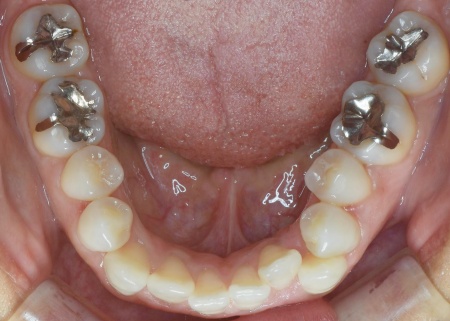

「奥歯で噛むと上下前歯が触れ合わないので、噛み合わせを治したい。また、歯並びがデコボコしているのも気になる」とご相談いただきました。

拝見したところ、奥歯で噛んだ際に上下の前歯が触れ合わず、隙間ができている状態でした。

これは開咬(かいこう)と呼ばれ、前歯で食べ物を噛み切るのが難しい噛み合わせです。

加えて全体的に歯が重なり合ってデコボコに生えており、歯磨きがしにくく、審美性にも悪影響がでています。

さらに舌で前歯を押す癖もあり、これは開咬の原因だけでなく、矯正治療後に歯並びが戻る原因にもなります。